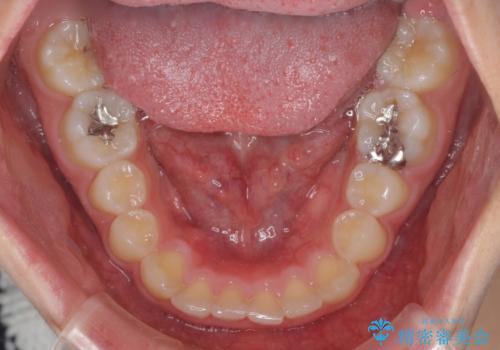

前歯のデコボコと突出感 インビザラインによる矯正治療

- 上下前歯のデコボコと、上顎前歯の突出感を気にして来院された患者様です。

インビザラインによる上下歯列の側方拡大と後方移動、IPR(歯と歯の間を削る)にるスペースの獲得により歯列を整えることとしました。

毎日22時間以上しっかりとマウスピースを装着していただいたので、スムーズに治療が進みました。歯と歯の間を削ることでうまくスペースコントロールでき、1年強で終えることができました。